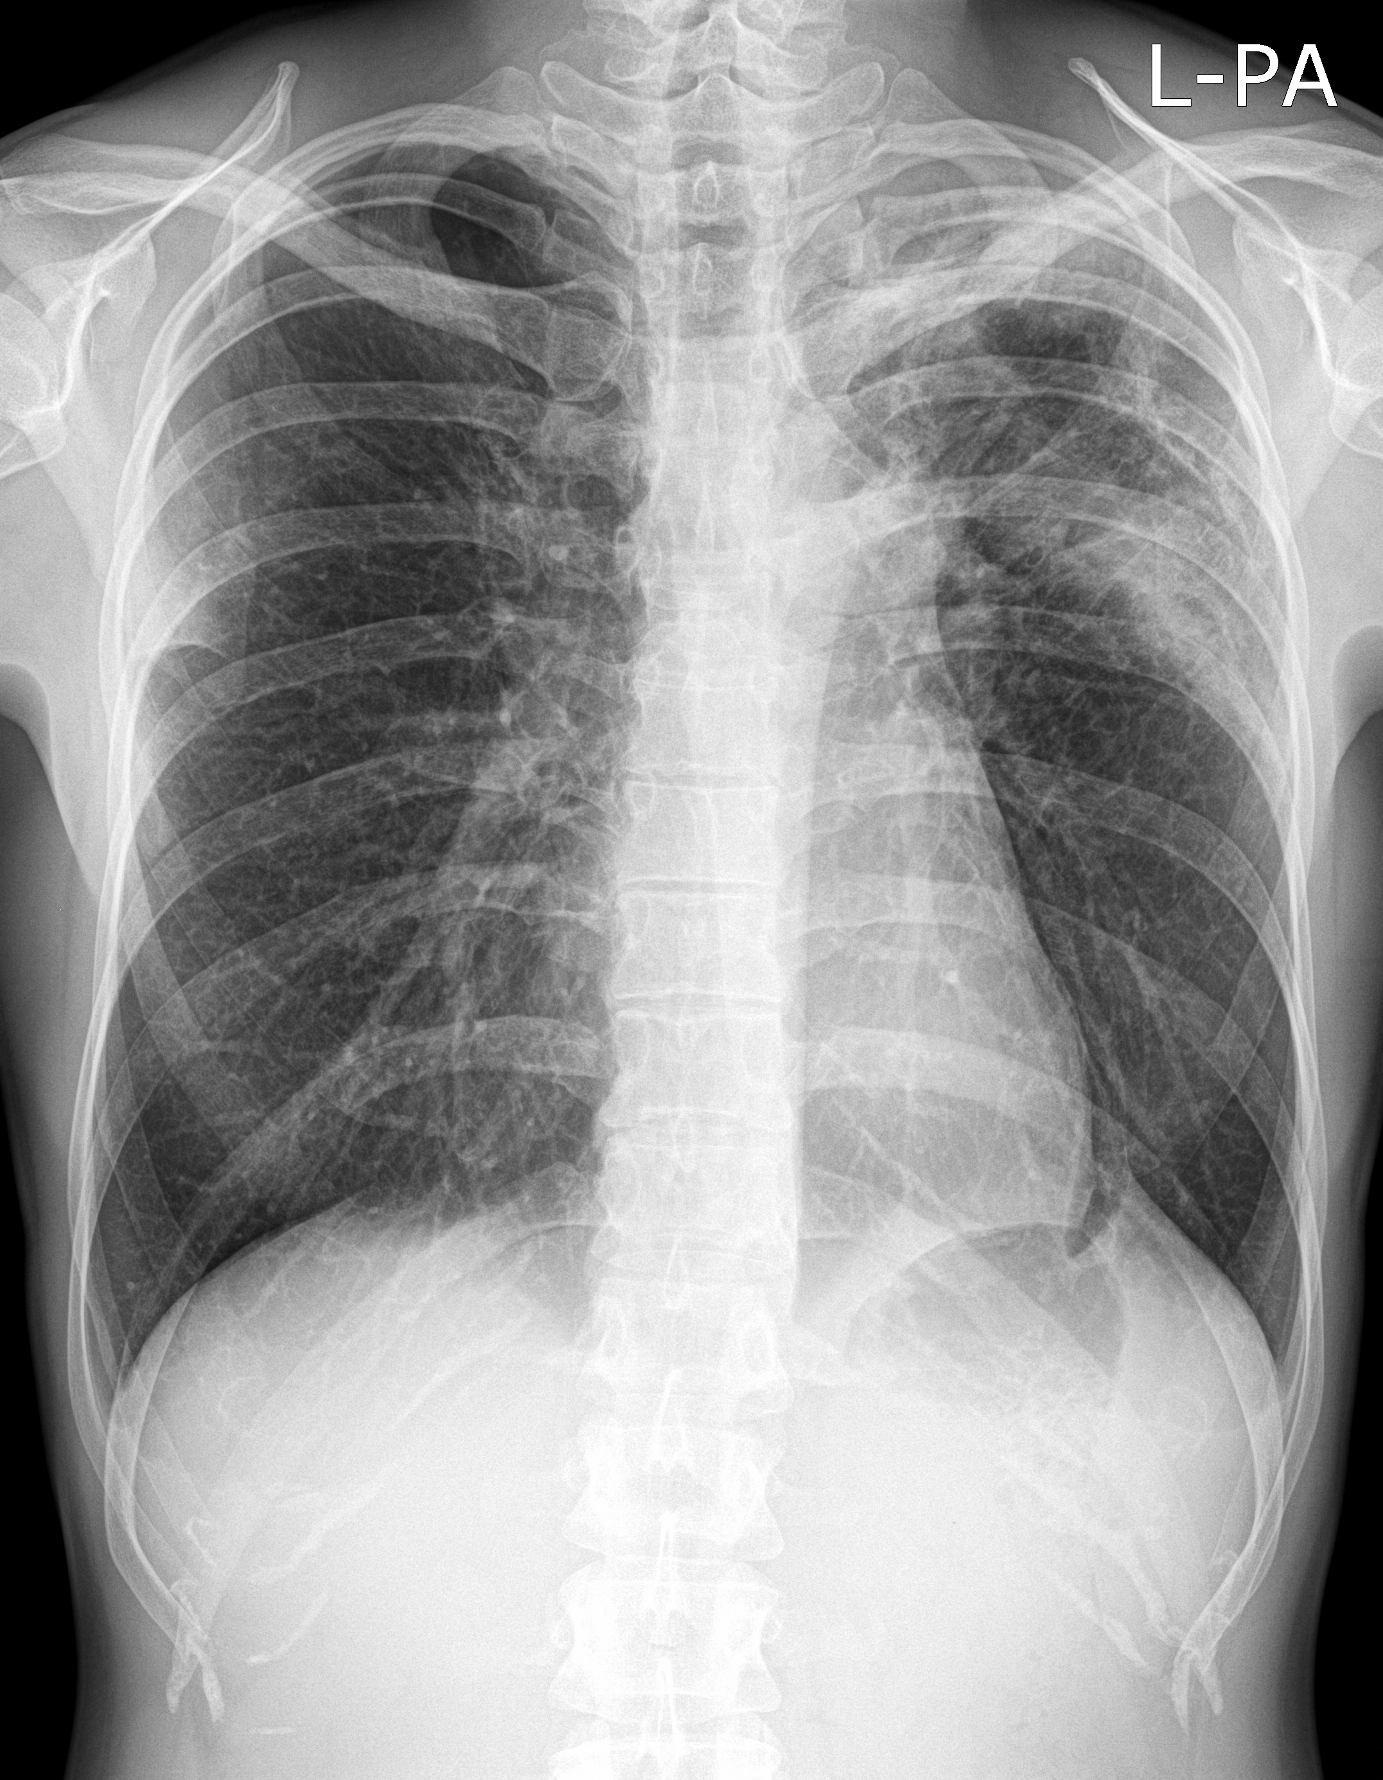

3a: Round shadow: multiple lung metastasis. Chest radiograph (PA)

3b: Multiple lung metastasis, CT lung window (axial, coronal reformat)

3c, coronal reformat

70 year old man, colon tumor.

Radiograph: Bilateral extensive, confluating patchy-nodular shadowing with diffuse reticular pattern. The diaphragm contour is partially blurry bilaterally: lymphangiosis carcinomatosa.

CT: Numerous 1-6 cm round and irregular, lobulated-spiculated contrast enhancing lesions in both lungs, everywhere sporadically.